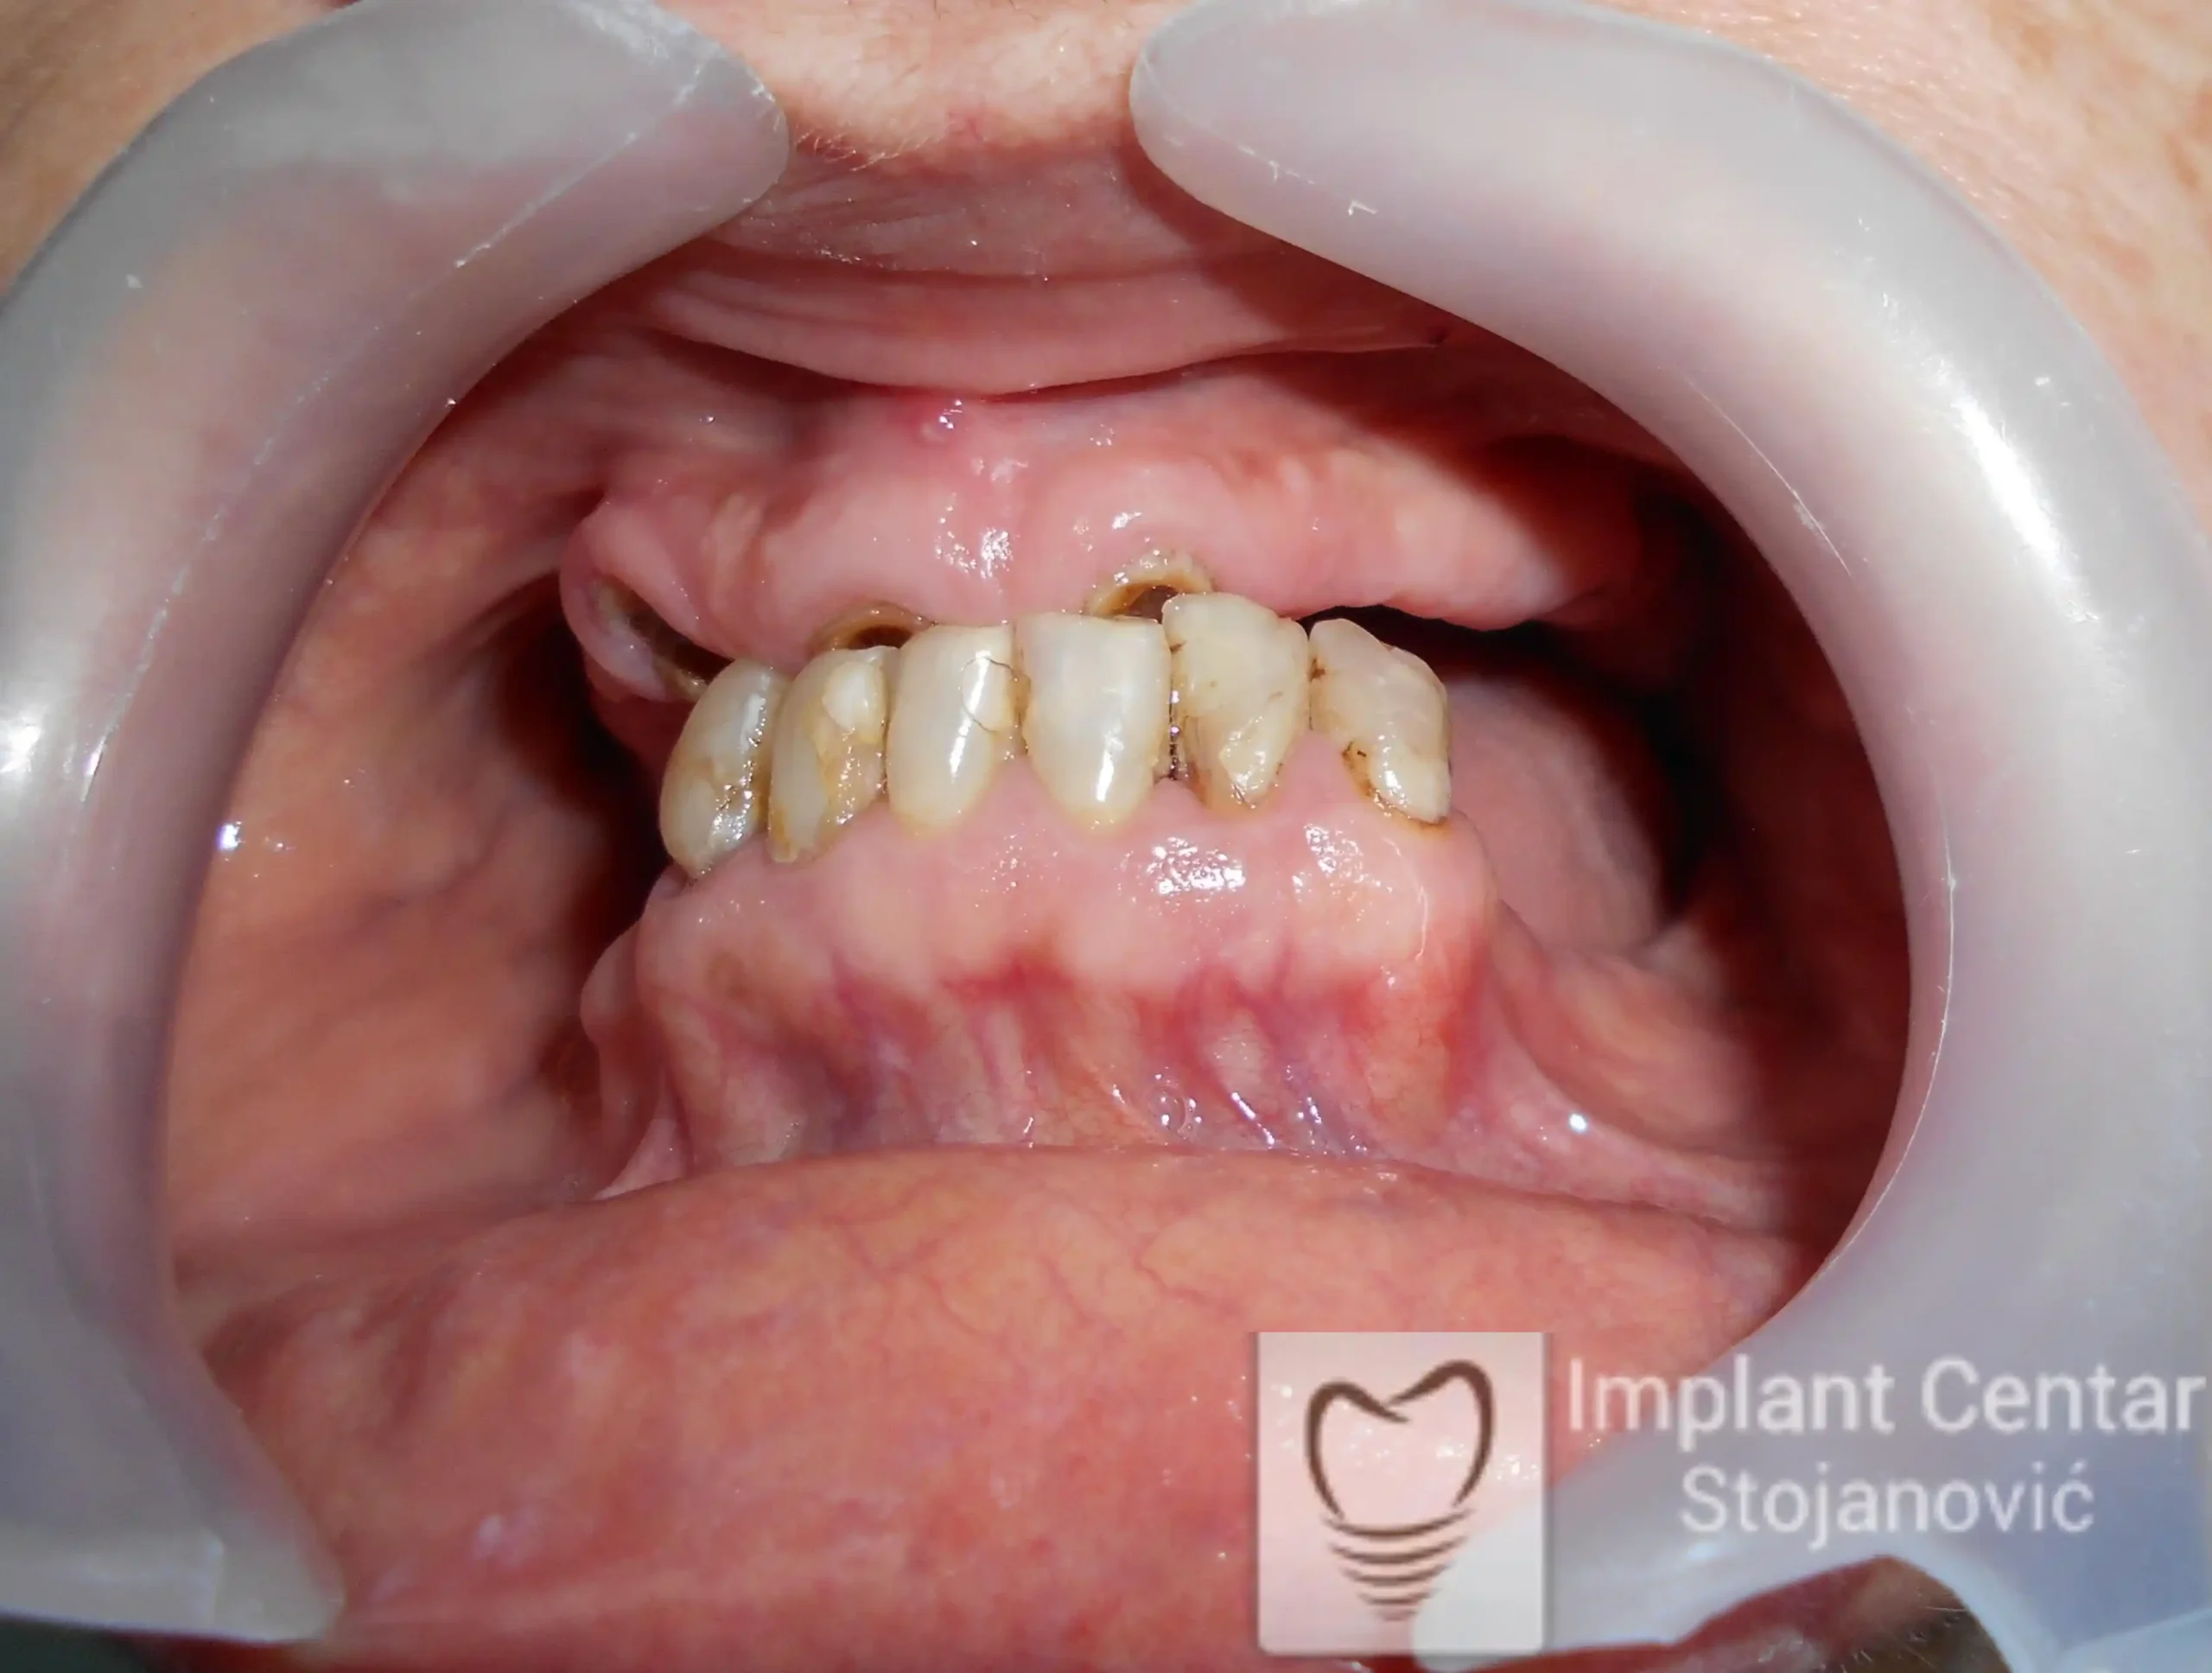

Pacijent sa rascepom usne, nepca i alveolarnog grebena uspešno je rehabilitovan fiksnim protetskim radom na implantatima. Pre dolaska u našu ordinaciju, pacijent je u gornjoj vilici nosio totalnu protezu preko preostalih zuba, dok je u donjoj vilici bio zbrinut parcijalnom mobilnom protezom. Tokom višegodišnje potrage za adekvatnim rešenjem, pacijent nije uspeo da pronađe zadovoljavajuću terapijsku opciju ni u zemlji ni u inostranstvu.

Nakon detaljnog kliničkog pregleda i analize radioloških snimaka, izrađen je sveobuhvatan plan terapije sa ciljem uklanjanja mobilnih proteza i postizanja maksimalne funkcionalne i estetske rehabilitacije. Zbog loše biološke vrednosti preostalih zuba, doneta je odluka o njihovom vađenju i ugradnji dentalnih implantata.